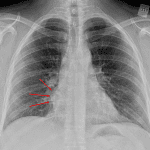

- Smoothly marginated soft tissue mass adjacent to the right heart border, likely in the anterior mediastinum

- No evidence of acute cardiopulmonary disease

- Anterior mediastinal mass (thymoma)

Smoothly marginated soft tissue mass adjacent to the right heart border, likely in the anterior mediastinum.

- CT was obtained and showed an anterior mediastinal mass that turned out to be a thymoma

- The boundaries of the anterior mediastinum include the right and left heart borders and ascending aorta. Therefore, bulging of these contours can be seen with an anterior mediastinal mass